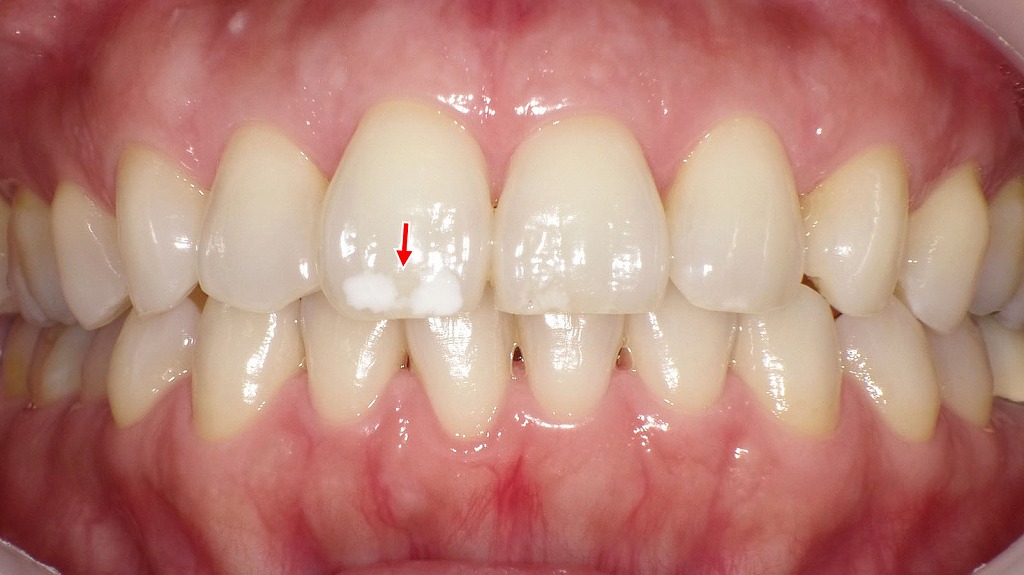

1枚目の画像:術前

ホワイトニング前の上顎前歯の状態です。

歯の表面に白斑(ホワイトスポット)は存在していますが、歯全体の色調がやや黄味を帯びているため、周囲の歯質とのコントラストが弱く、比較的目立ちにくい状態です。

2枚目の画像:ホワイトニング後

ホワイトニング後の上顎前歯です。

歯全体が明るく白くなったことで、エナメル質内の白斑(ホワイトスポット)が周囲との色差により、以前よりもはっきりと目立つようになっています。

ホワイトニングによって歯が白くなる一方、このようにホワイトスポットが強調されるケースもあります。